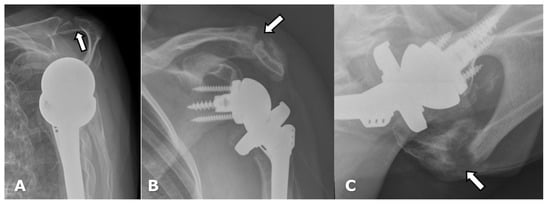

4.3. Unique Complications

- Torrens, C.; Guirro, P.; Miquel, J.; Santana, F. Influence of glenosphere size on the development of scapular notching: A prospective randomized study. J. Shoulder Elb. Surg. 2016, 25, 1735–1741. [Google Scholar] [CrossRef] [PubMed]

- Sirveaux, F.; Favard, L.; Oudet, D.; Huquet, D.; Walch, G.; Mole, D. Grammont inverted total shoulder arthroplasty in the treatment of glenohumeral osteoarthritis with massive rupture of the cuff. Results of a multicentre study of 80 shoulders. J. Bone Jt. Surg. 2004, 86, 388–395. [Google Scholar] [CrossRef] [PubMed]

- Torrens, C.; Miquel, J.; Martínez, R.; Santana, F. Can small glenospheres with eccentricity reduce scapular notching as effectively as large glenospheres without eccentricity? A prospective randomized study. J. Shoulder Elb. Surg. 2019, 29, 217–224. [Google Scholar] [CrossRef]

| Grade | Finding |

|---|---|

| 1 | Lucency extends to scapular pillar |

| 2 | Lucency contacts the inferior glenoid screw |

| 3 | Lucency extends over the inferior glenoid screw |

| 4 | Lucency extends under the metaglene/baseplate |